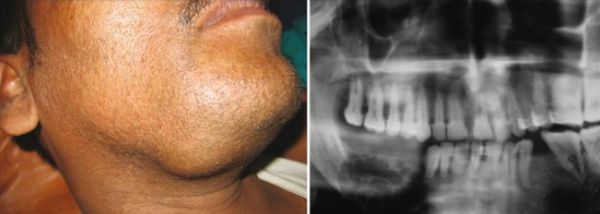

Амелобластома (Ameloblastoma) — это доброкачественная опухоль, которая развивается из зубообразующих тканей. По мере её роста деформируются черты лица, смещаются и расшатываются зубы.

Амелобластома развивается медленно и бессимптомно, чаще возникает в области угла и ветви нижней челюсти. Почти никогда не вызывает воспаления.

![Амелобластома [11]](/pimg3/opuxoli-kostey-lechenie-26CD06.jpeg)

- Рентгенограмма (ортопантомограмма) — на двухмерном снимке видна опухоль с характерными признаками амелобластомы (поражение в виде мыльных пузырей), что позволяет предположить этот диагноз.

Амелобластома – наиболее частая одонтогенная опухоль челюстей, склонная к инвазивному, местно-деструирующему росту. Поражает преимущественно нижнюю челюсть в области ее тела, угла или ветви. Развивается внутрикостно, может прорастать в мягкие ткани дна полости рта и десны. Чаще проявляется в возрасте 20-40 лет.

В начальном периоде амелобластома протекает бессимптомно, однако по мере увеличения размеров опухоли возникает деформация челюсти, асимметрия лица. Зубы в области поражения часто становятся подвижными и смещаются, может отмечаться зубная боль. Опухоль верхней челюсти может прорастать в полость носа, гайморову пазуху, орбиту; деформировать твердое нёбо и альвеолярный отросток. Нередки случаи нагноения, рецидивирования и малигнизации амелобластомы. Клиническое течение таких опухолей челюсти, как амелобластическая фиброма и одонтоамелобластома, напоминает амелобластому.